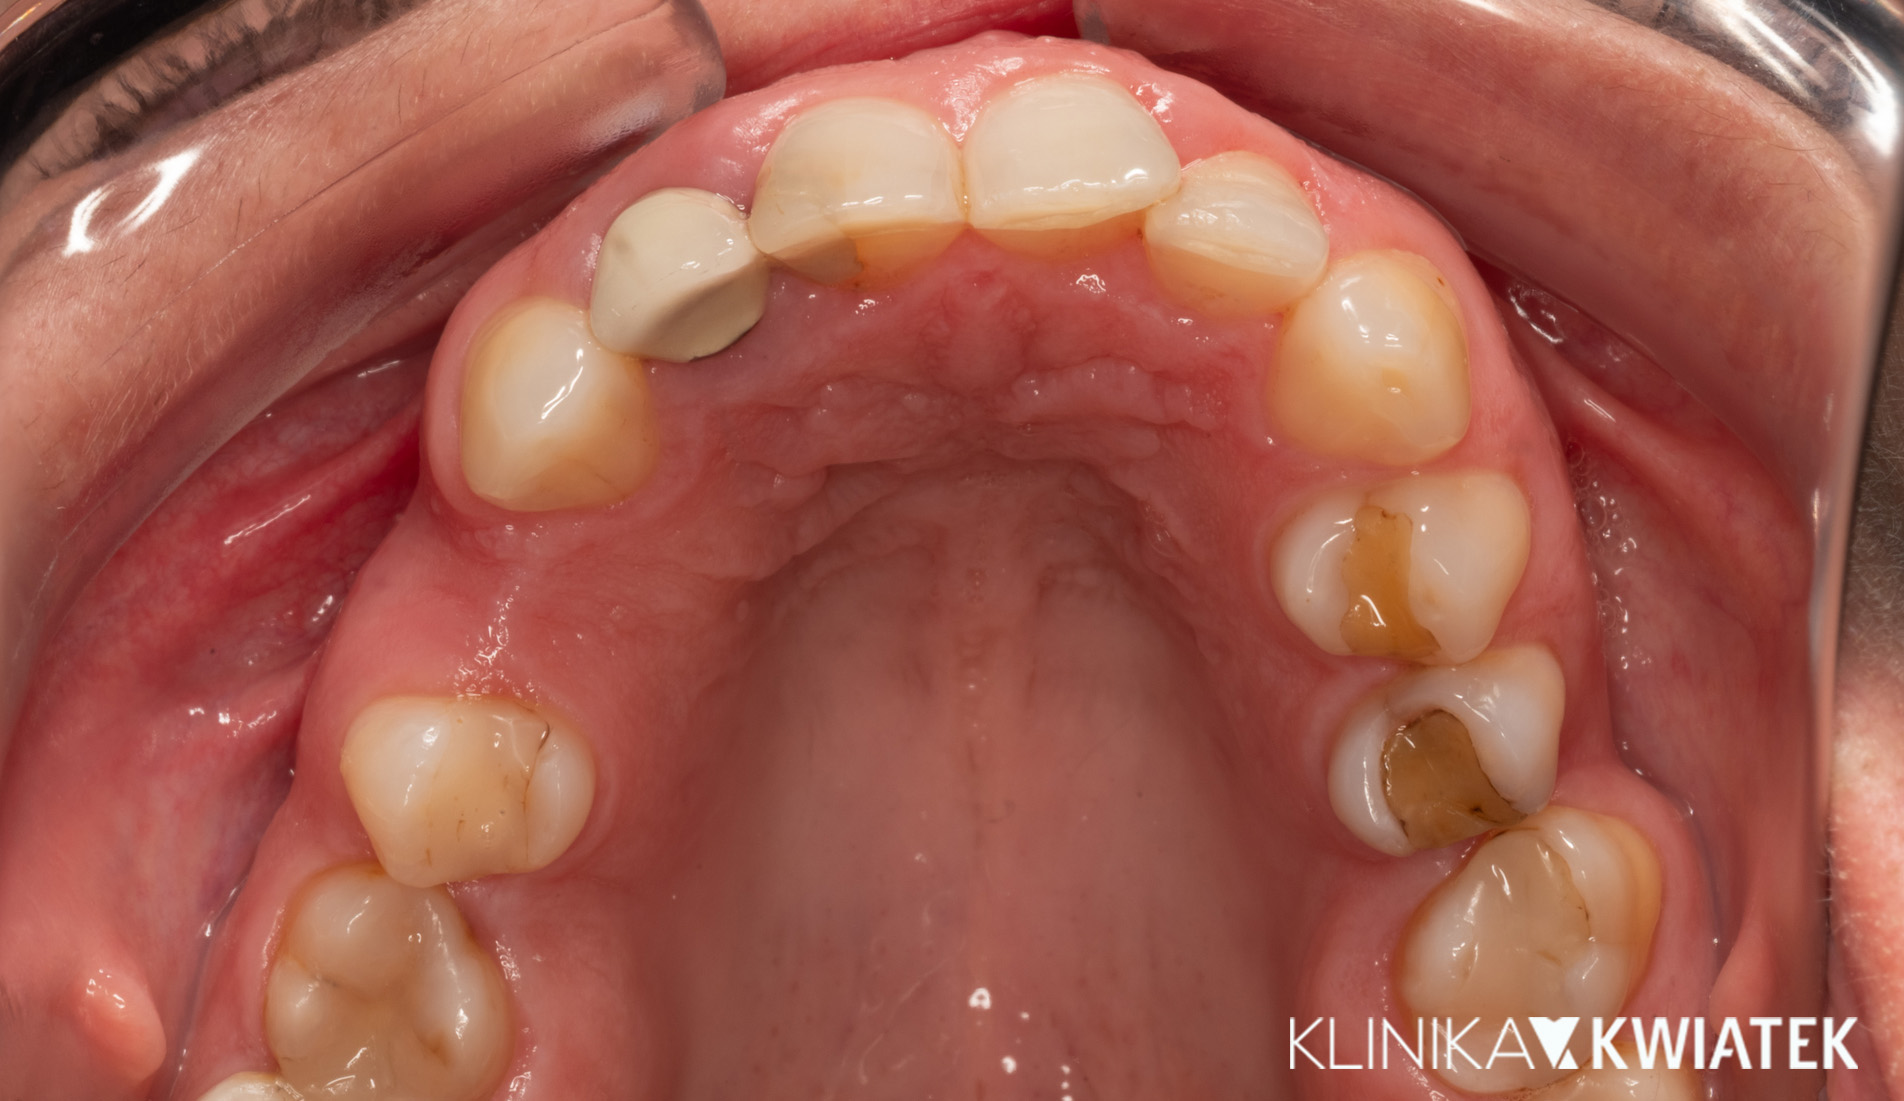

Jak uśmiech pokonał strach – metamorfoza pełna zaufania

Pacjent przez wiele lat unikał wizyt u dentysty z powodu silnego lęku. Strach przed leczeniem sprawił, że w jamie ustnej pojawiły się rozległe zmiany próchnicowe i liczne zęby wymagały ekstrakcji.

Po dokładnej diagnostyce i rozmowie, wiedząc, że Pacjent wyklucza leczenie ortodontyczne, krok po kroku wdrożono kompleksowy plan leczenia – od higienizacji i leczenia zachowawczego, przez zabiegi chirurgiczne i endodontyczne, aż po odbudowę braków zębowych na implantach.

Dziś Pacjent z dumą i spokojem uśmiecha się bez lęku – cieszy się zdrowym, estetycznym uśmiechem, stabilnym zgryzem i doskonałą higieną jamy ustnej.